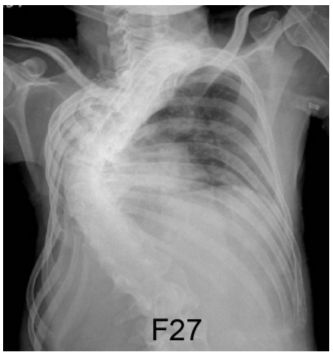

1. 女性21歲,未吸煙,主訴長期呼吸困難。胸部X光如圖。 可預期會出現下列肺部異常,何者除外? (A) 侷限性肺部疾病 (B) 肺泡換氣低下 (hypoventilation) (C) 阻塞性肺部疾病 (D) 換氣-灌注 (V-Q) 異常 (E) 肺動脈高壓症